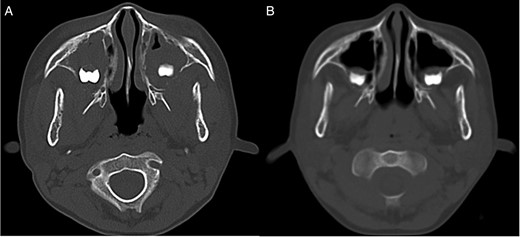

A CT examination performed with contrast showed enhancing bilateral expansile masses (right: 3.8 × 3.7 × 2.5 cm, left 3.5 × 3.1 × 2.5 cm) within the maxillary sinuses, with osteolysis of the posterior walls (Fig. 1A).

CT image. (A) CT image showing bilateral mass lesions within the maxillary sinuses, with osteolysis involving the posterior walls (right: 3.8 × 3.7 × 2.5 cm, left 3.5 × 3.1 × 2.5 cm). (B) CT image after one course of chemotherapy showing partial reduction of the masses.

The masses in the maxillary sinuses involved the maxillary wisdom teeth. The wisdom tooth begins as a tooth germ at 4 years of age and begins to form a crown with calcification at 7 years. If lymphoma cells appear in the maxilla during this time, the crown may be covered with lymphoma, giving a dentigerous cyst-like appearance on CT as seen in Fig. 1A.